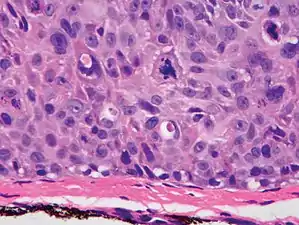

Histopathologically, the epidermis in cSCC in situ (Bowen's disease) will show hyperkeratosis and parakeratosis. There will also be marked acanthosis with elongation and thickening of the rete ridges. These changes will overly keratinocytic cells which are often highly atypical and may in fact have a more unusual appearance than invasive cSCC. The atypia spans the full thickness of the epidermis, with the keratinocytes demonstrating intense mitotic activity, pleomorphism, and greatly enlarged nuclei. They will also show a loss of maturity and polarity, giving the epidermis a disordered or "windblown" appearance.

Two types of multinucleated cells may be seen: the first will present as a multinucleated giant cell, and the second will appear as a dyskeratotic cell engulfed in the cytoplasm of a keratinocyte. Occasionally, cells of the upper epidermis will undergo vacuolization, demonstrating an abundant and strongly eosinophilic cytoplasm. There may be a mild to moderate lymphohistiocytic infiltrate detected in the upper dermis.[12]